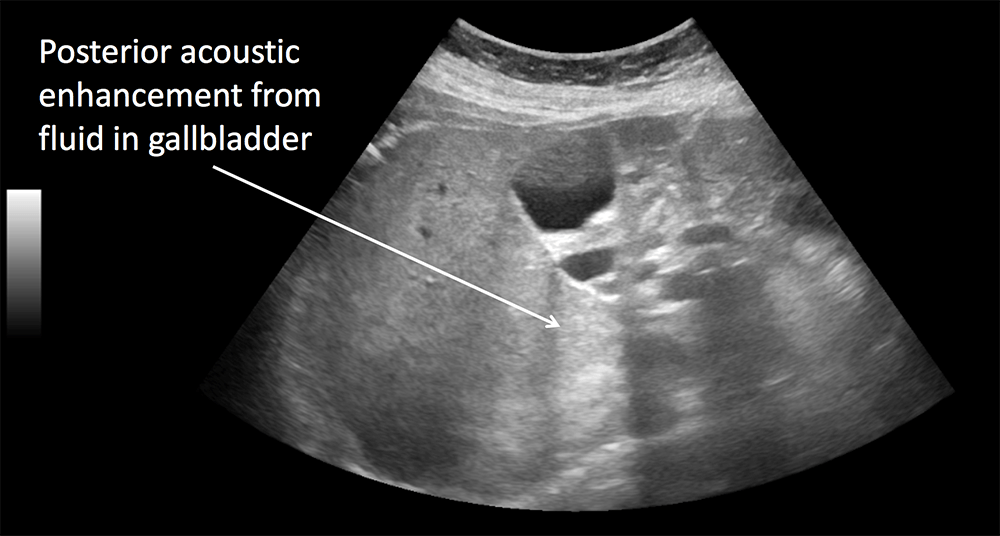

Acoustic Artifacts . Some structures have very high echogenicity (e.g skeleton, calcifications, mechanical heart valves) and reflect virtually all sound waves, leaving too few waves to explore the area behind the reflector. Figure 1 shows acoustic shadowing bellow a gallstone. The main restrictions of an axial and lateral resolution are artifacts. This document discusses various types of artifacts that can appear in ultrasound images, including reverberation, acoustic shadowing, enhancement, edge. This results in dark areas, which are referred to as acoustic shadows. In some cases, specific artifacts. Acoustic enhancement also called posterior enhancement or enhanced through transmission, refers to the increased echoes. However, failure to fix them lead to the lack of details, and adjacent neighboring objects may be. Ultrasound artifacts are commonly encountered and familiarity is necessary to avoid false diagnoses.